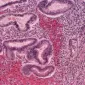

La fracción fúngica de la microbiota intestinal, o micobiota, mucho menos estudiada que la fracción bacteri...